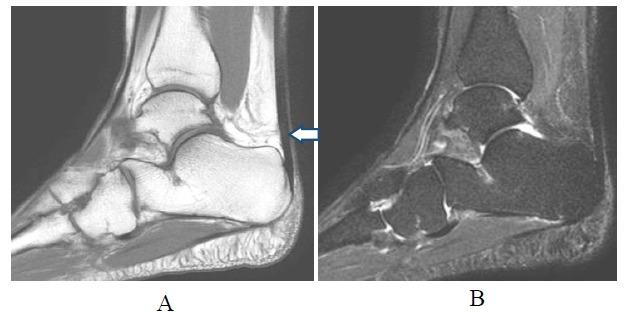

手术修复后跟腱的磁共振成像

MR Imaging of the Achilles Tendon after Surgical Repair.

Achilles tendon tear is common and increasingly frequent. Magnetic resonance imaging (MRI) is the modality of choice for radiological evaluation. It is accurate to assess the status and integrity of the tendon with well documented features. In this article, the MR findings of a normal Achilles tendon as well as common diseases like insertional and noninsertional tendinosis, chronic tendinosis with marked lengthening, tendon rupture are illustrated. After a torn Achilles tendon receives surgical repair, it undergoes different stages of healing process including inflammatory, reparative and remodeling phases. Acute scar tissue in the surgical bed may share similar MR features of tendon re-rupture especially in the early healing phase because both are T2W hyperintense. The size of the gap may even appear larger than expected on T2W images possibly due to tendon remodeling. Understanding of the healing process in post-operative period may prevent overestimation of tendon gap and misdiagnosis of re-tear. We describe the MR features of the post-operative changes with serial studies in different months after surgery. The MR findings with the highlights of the expected sequential changes in normal healing process are illustrated in different cases. A case with surgical repair on a partial tear of Achilles tendon is also included.

摘要

跟腱撕裂很常见且愈发频发。磁共振成像(MRI)是放射学评估的首选方式。它能够准确评估肌腱的状态和完整性,且具有充分记录的特征。在本文中,展示了正常跟腱的磁共振成像表现以及诸如附着点和非附着点肌腱病、伴有明显延长的慢性肌腱病、肌腱断裂等常见疾病的表现。跟腱撕裂接受手术修复后,会经历不同的愈合阶段,包括炎症期、修复期和重塑期。手术部位的急性瘢痕组织可能具有与肌腱再次断裂相似的磁共振成像特征,尤其是在愈合早期,因为二者在T2加权像上均呈高信号。在T2加权像上,间隙大小甚至可能看起来比预期更大,这可能是由于肌腱重塑所致。了解术后愈合过程可避免对肌腱间隙的高估以及对再次撕裂的误诊。我们通过对术后不同月份的系列研究来描述术后改变的磁共振成像特征。在不同病例中展示了磁共振成像表现以及正常愈合过程中预期的连续变化要点。还纳入了一例跟腱部分撕裂手术修复的病例。